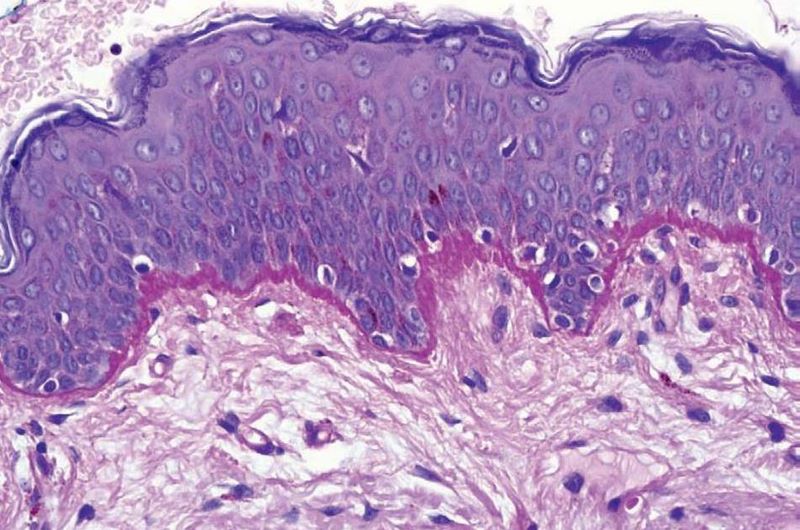

CLdermatopat --Unión dermo-epidermica. La membrana basal en

microscopía óptica se obseva como una membrana amorfa eosinofilica que se tiñe

positivamente con la tinción de PAS